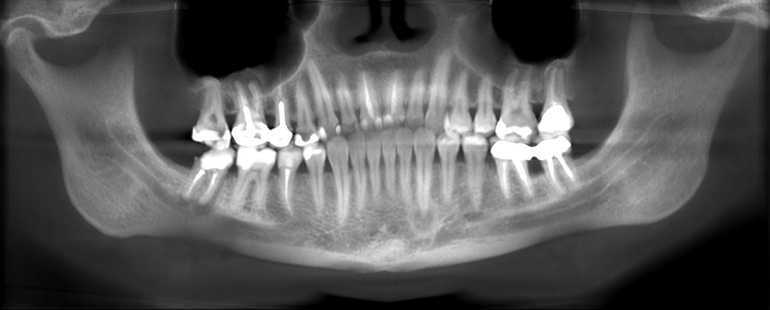

Пошла к стоматологу, снимок показал приличную кисту нижней правой семёрки. Доктор предложил лечение на полгода: паста метапекс и временная пломба, всё это будет меняться раз в месяц. В первый месяц упала стена зуба, потом ещё часть. От начала лечения прошло 3 месяца.

В свете планирования второй беременности решила сделать КТ.

Доктор клиники,в которой сделали томографию сказал, что по КТ есть трещина корня проблемного зуба и зуб на удаление. И ещё есть 2 проблемных верхних зуба - кисты. Один из них - правая шестёрка под коронкой и там что-то похожее на обломки инструмента. Второй - левая семёрка. Всё это нужно перелечивать.